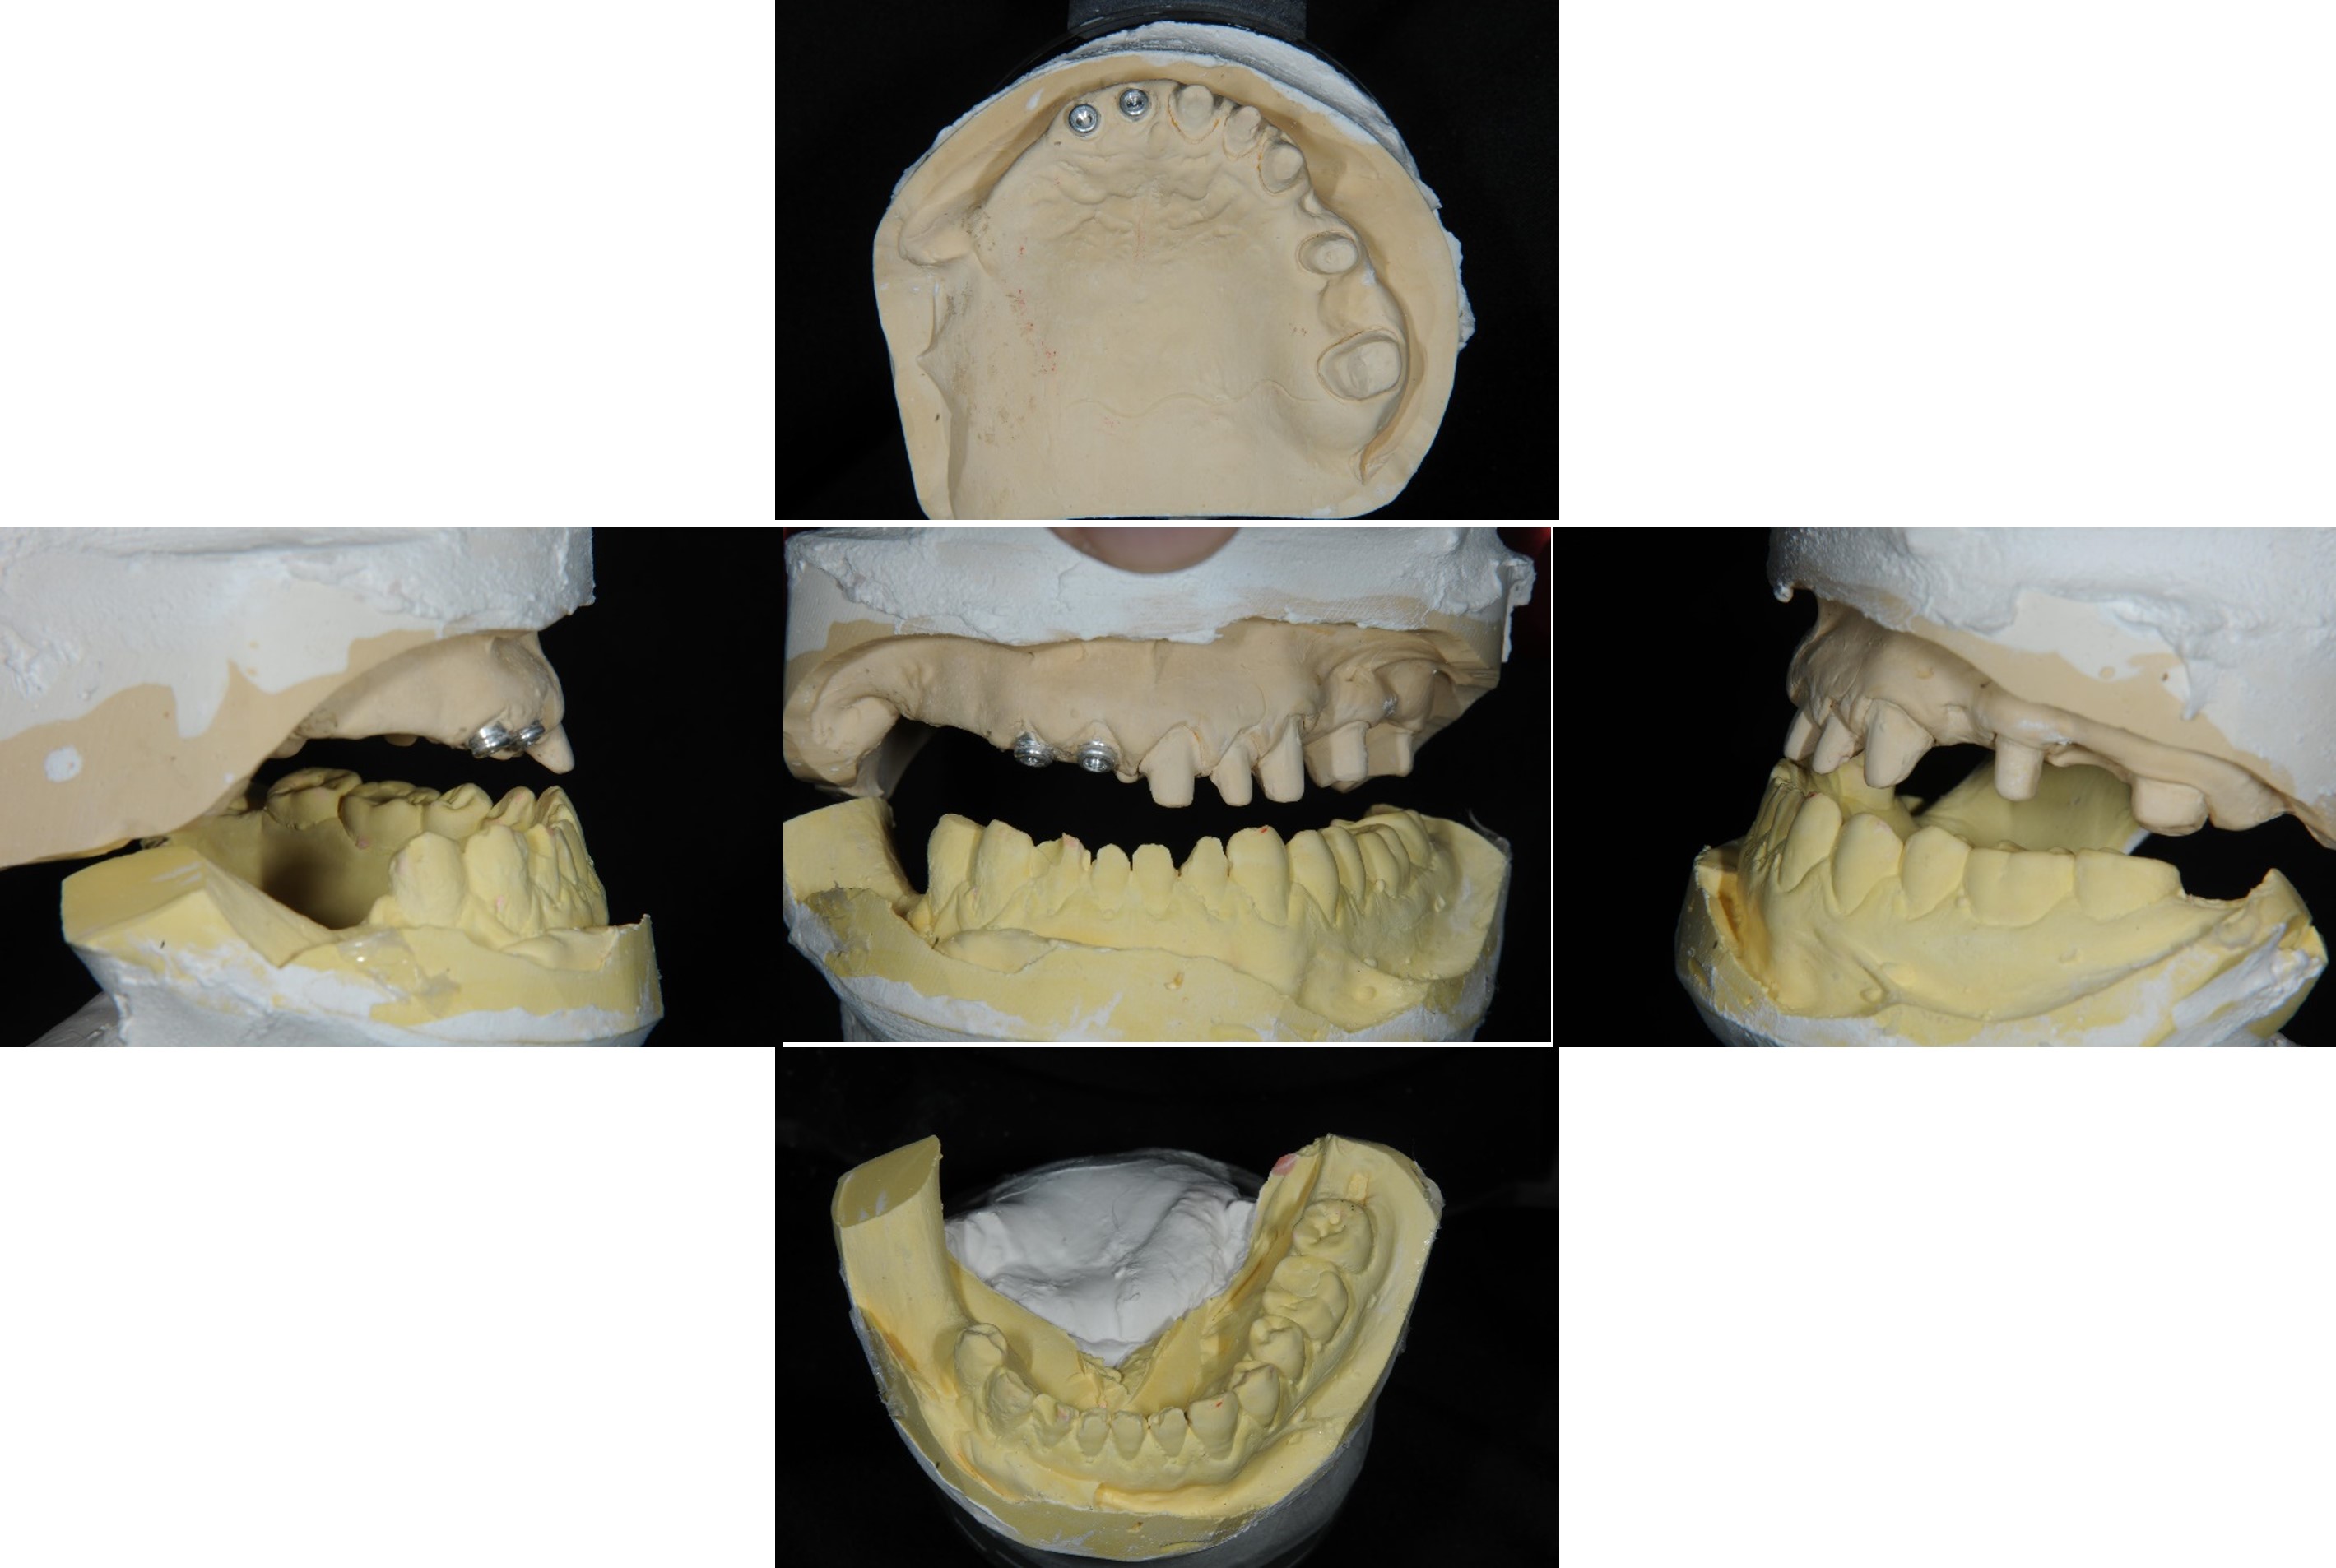

模型咬合分析

上咬合器

繼續咬合器製作